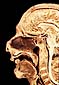

Pared Lateral de las Fosas Nasales